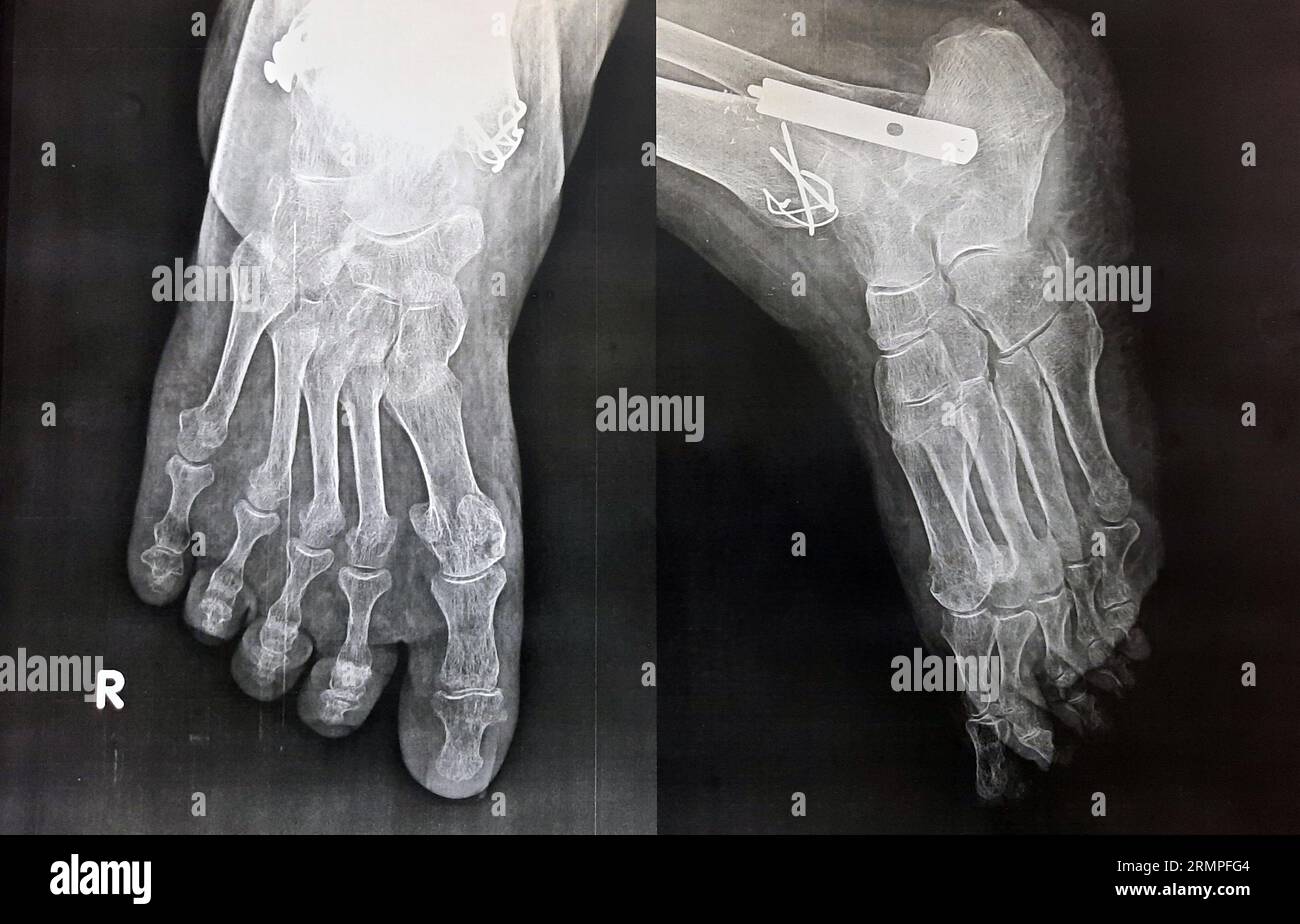

Fractura conminuta de quinto metatarsiano en un deportista profesional Quinto Hueso Metatarsiano Roto Se explica cómo se diagnostica, cómo se trata y cómo se previene esta fractura, con ejemplos de casos famosos y consejos del dr. La fractura del 5º metatarsiano del pie es una lesión común entre los deportistas, que suele ocurrir por un mal salto o esguince. Aprende cómo se clasifica, se trata y se recupera la fractura de los metatarsianos. Quinto Hueso Metatarsiano Roto.

Opciones de tratamiento de la fractura del quinto metatarsiano Quinto Hueso Metatarsiano Roto Estos son algunos ejemplos de ejercicios que usted puede probar. La fractura del quinto metatarsiano es una fractura muy habitual en la población que en la mayoría de las ocasiones se repara sin dejar ningún problema secundario. Aprende cómo se clasifica, se trata y se recupera la fractura de los metatarsianos del pie, según el número, el desplazamiento y la. Quinto Hueso Metatarsiano Roto.